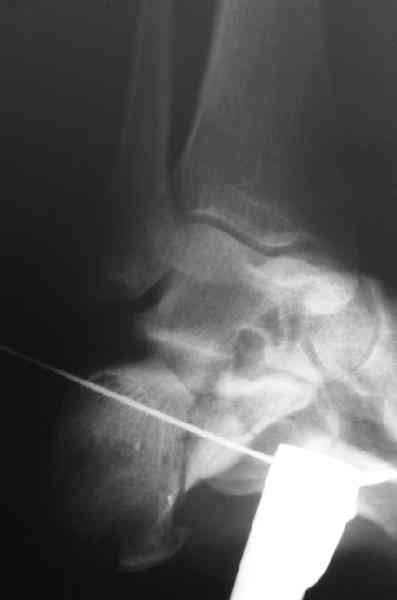

Открытый и закрытый способы лечения.

Вправление задней фасеты с восстановлением таранно-пяточного угла возможно минимально-инвазивным методом Essex-Lopresti - под ЭОП или графическим контролем введенной в пяточный бугор толстой спицей или стрежнем Штеймана, которые служат рычагом. Для удержания вводим несколько тонких спиц Киршнера, фиксация в эквинусе.Подробнее в Margo anterior 1-2 2000\издание АО Матис в России, на сайте www.mathys.ru в архиве есть все выпуски. Метод внедрен у нас с 2000 года и дает неплохие результаты.

Действительно архив Margo Anterior начинается с 2001 года.Но я могу эту статью по лечению переломов пяточной кости,очень обстоятельную, санировать и выслать мылом на ваш адрес или разместить на rapidshare ru и указать ссылку на форуме. несколько тонких спиц вводятся в разных направляениях при многофрагментарных переломах иногда через подтаранный сустав для удержания репозиции. Их и стержень удалем через 6 недель.